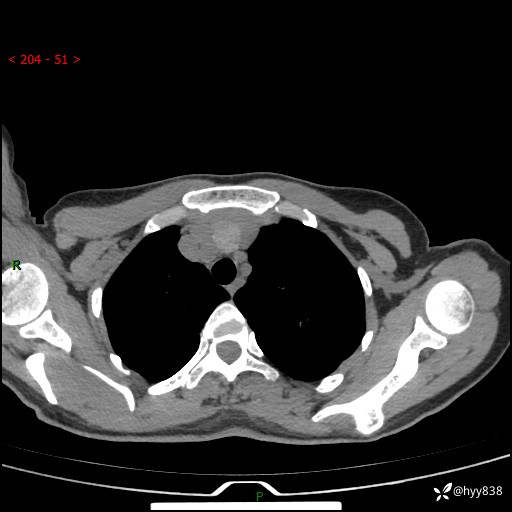

胸部CT平扫